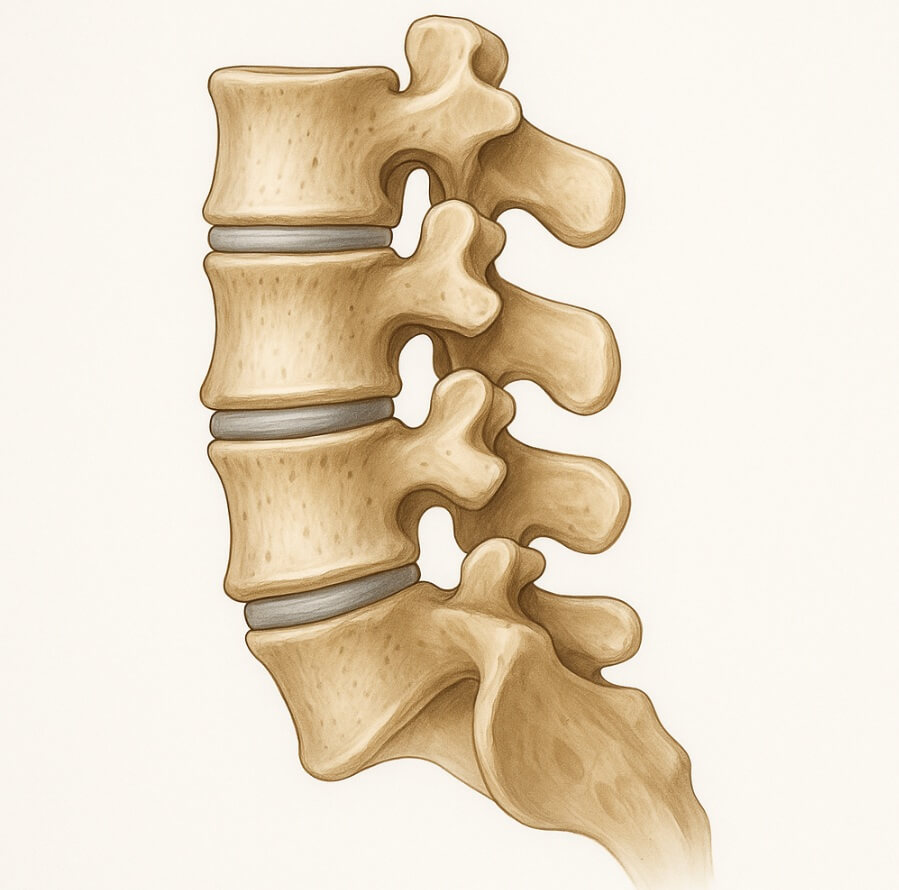

척추관 협착증은 신경이 눌리는 ‘신경근성 간헐적 파행’ 증상 때문에 허리를 굽혔을 때 통증이 줄어드는 특징이 있습니다. 따라서 허리를 ‘앞으로 굽히는(flexion)’ 스트레칭이 통증 경감에 효과적입니다.

척추과 협착증 운동법 아래 그림을 보면서 따라해 보세요!!!!!!!

- 무릎 당기기(Knee-to-Chest) – 등을 대고 무릎을 세운 자세에서 한쪽 무릎을 천천히 가슴 쪽으로 당깁니다. 15초 유지 후 반대쪽, 총 3세트. 허리가 바닥에 완전히 닿도록 복근에 힘을 주세요.

- 고양이-낙타(Cat-Camel) – 네발 자세에서 숨을 내쉬며 등을 둥글게 말아 신경 공간을 넓히고, 들이쉬며 중립으로 돌아옵니다(허리를 과도하게 젖히지 않기). 10회×2세트.

- 앉아서 몸 앞으로 숙이기(Seated Forward Flexion) – 의자에 앉아 상체를 허벅지 위로 자연히 숙여 20초간 호흡. 대중교통에서 통증이 올라올 때 응급 스트레칭으로 유용합니다.

모든 스트레칭은 날숨에 긴장을 풀어 근육을 이완하고, 통증이 5점(10점 만점) 이상이면 즉시 중단해야 합니다.